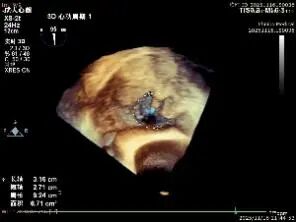

Left Atrial Appendage Closure (LAAC):The delivery system was successfully advanced into the left atrium. Precise measurements of the LAA orifice and depth were taken under multi-angle TEE and DSA guidance. Given the LAA's large orifice (nearly 34mm), conical cauliflower shape, and shallow usable depth, a LACBES2434 occluder was selected. Using the "extreme coin technique," the closure was successfully achieved.

Echocardiographic Assessment: Echocardiography revealed left atrial enlargement. The left atrial appendage (LAA) orifice was 32mm with no thrombus inside. Tricuspid regurgitation was extreme (average vena contracta 18mm). Regurgitant jets were located at the anterior-septal, central, and posterior-septal commissures, with a central gap measuring approximately 13x5.9mm. The annulus was mildly dilated (average diameter 43mm). The tricuspid leaflets showed thickening and degenerative changes.

CTA Assessment: Showed a giant, wide-mouthed, conical "cauliflower-shaped" LAA. The right coronary artery (RCA) runs toward the atrial side, with a distance greater than 3mm between the RCA and the annulus during both systole and diastole.